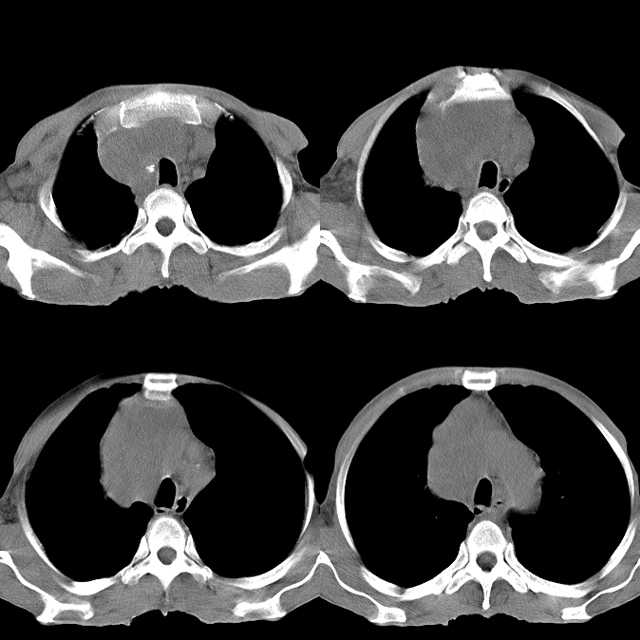

以下是引用心路寻觅在2010-4-17 18:35:00的发言:[br]纵膈多组淋巴结肿大呈“冰冻纵膈”,左肺上叶空洞伴其内结节密度影,考虑淋巴瘤伴左肺上叶曲霉菌感染。[br][br][本贴已被 心路寻觅 于 2010-4-17 18:36:23 修改过]

以下是引用zhangzhongshou在2010-4-17 19:32:00的发言:[br]一元论考虑左肺空洞型肺癌并纵隔淋巴结转移可能性大。